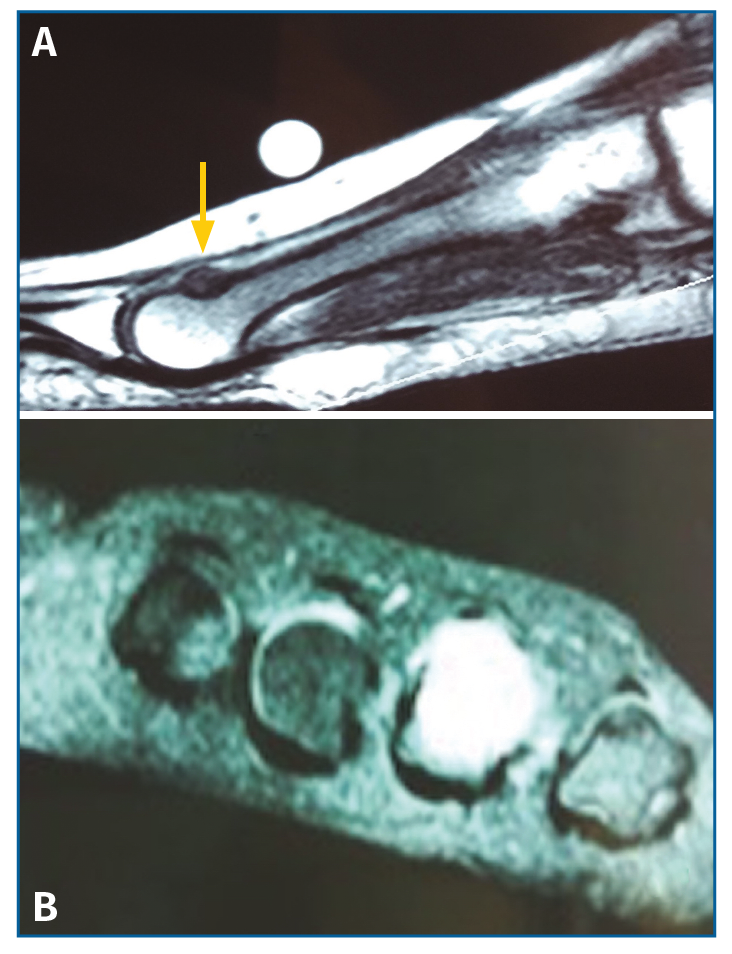

Con el objetivo de determinar las características de la lesión detectada en la RM, se indicó una gammagrafía ósea con tecnecio en 3 fases, que mostró un foco de hipercaptación de morfología redondeada en la cabeza del cuarto metatarsiano, compatible con una fractura de estrés (Figura 4). Una nueva RM en dispositivo convencional de 3T permitió detectar una lesión de 6 mm de diámetro en el dorso del cuello del cuarto metatarsiano, compatible con un osteoma osteoide (OO) (Figura 5). La TC de cortes finos a dicho nivel confirmó definitivamente la lesión tumoral (Figura 6).

Figura 5. Resonancia magnética en corte sagital (A) con imagen de lesión en el dorso del cuello del 4.º metatarsiano hipointensa en T1. En corte axial (B) se observa alteración de señal hiperintensa en T2 a nivel del 4.º metatarsiano.